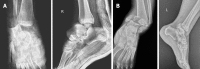

Case summary: We report a very rare injury of closed TTD with a follow-up period of 36 mo. Initial closed reduction was not successful because of a fractured highly unstable medial malleolus displaced into the ankle mortise, blocking the relocation of the talus. The patient was able to walk pain-free after the 3rd month of surgery. At the 36-mo follow-up, there were 10 degrees of flexion loss and 10 degrees of extension loss in the tibiotalar joint. Furthermore, 5 degrees of subtalar joint inversion-eversion loss was present.